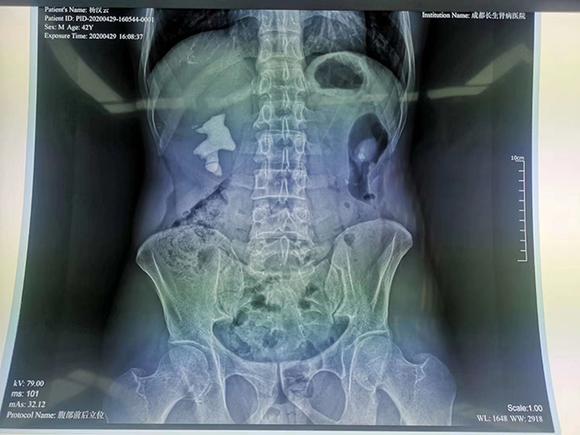

经诊断,杨先生双侧肾都有结石,左侧的结石直径1厘米左右,暂时不对肾功能造成影响,可不予处理;右侧是一个巨大的填满性铸型结石,直径5.0cm*4.5cm。右侧结石已经充满肾脏空间,如果不尽快取出,会进一步引发梗阻而造成肾功能破坏,也会因长期刺激肾脏而有癌变风险。